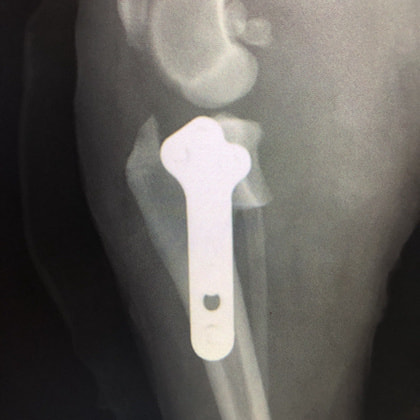

バーニーズマウンテンドック 4歳 避妊♀

突然の右後肢跛行を主訴に来院されました。整形外科学的検査において右膝に脛骨圧迫テストで陽性、前方引き出し徴候が認められました。神経学的検査において特に異常は認められませんでした。レントゲン検査において、関節液の貯留所見や脛骨の前方変位の所見が認められました。

関節鏡検査を実施いたしました。関節鏡検査では、重度の滑膜炎および前十字靭帯の完全断裂が認められました。半月板に損傷は認められませんでした。

断裂前十字靭帯の除去を行いました。その後 TTA(Tibial tuberosity advancement)を実施しました。

術後経過は良好で、後肢機能・筋肉量の改善目的で現在はリハビリテーションを行っています。